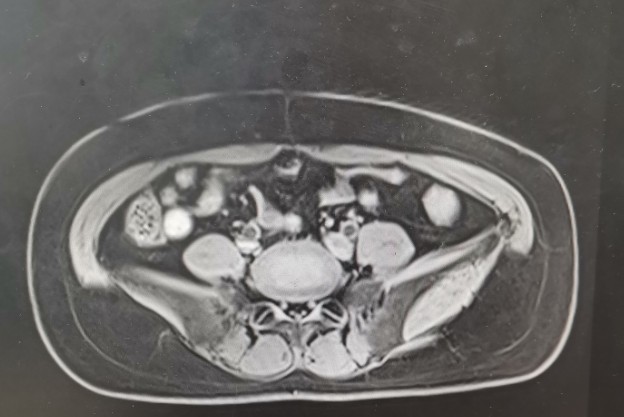

•全腹核磁:子宫术后改变,脂肪肝,双肾囊肿,盆腔少量积液。

轴位T1

轴位T2